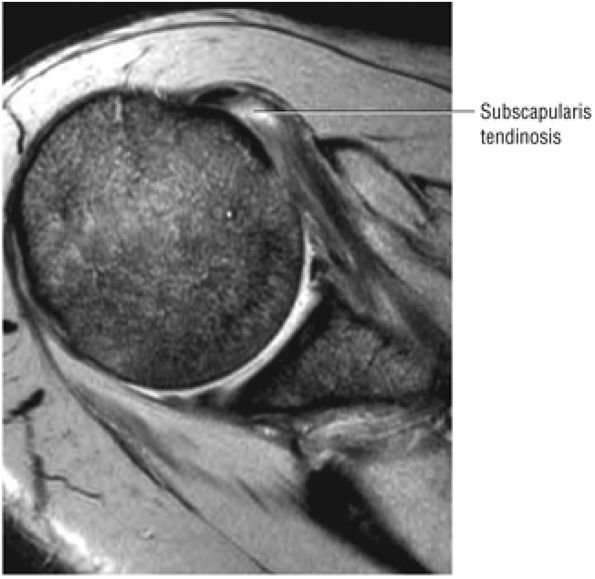

FIGURE 8.102 ● (A) The anterior undersurface of the acromion and the coracoacromial ligament form the coracoacromial arch. The subacromial subdeltoid bursa facilitates the passage of the rotator cuff and proximal humerus under the coracoacromial arch. (B) A superior axial image shows the anterior-to-posterior extent of the coracoacromial (CA) ligament perpendicular to the supraspinatus tendon. The fluid in the subacromial-subdeltoid bursa represents fluid between two serosal surfaces in contact with each other. One serosal surface is contributed by the undersurface of the coracoacromial arch and deltoid, and the other serosal surface is on the bursal side of the cuff.

|

![]() |

FIGURE 8.103 ● Pseudospur. The normal broad attachment of the coracoacromial ligament to the inferior surface of the acromion is shown on (A) T1-weighted coronal oblique and (B) sagittal oblique images. The low-signal-intensity acromial cortex (black arrows) and adjacent coracoacromial ligament and lateral slip of the deltoid attachment (white arrows) give the false impression of a small subacromial spur in the coronal plane. This pseudospur should not be misinterpreted as impingement; otherwise, unnecessary acromioplasties may be performed on patients with a normal coracoacromial ligament attachment and no associated acromial spurs.